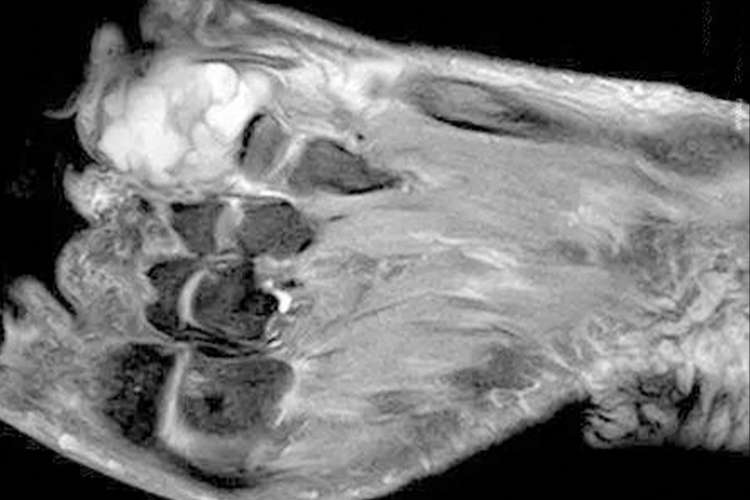

甲下骨疣表现为疼痛、肿胀,局部可见破溃和感染,病变部位多位于指端末节。X线上可以看到脚趾周围的硬的骨性包块,部分病变边界清楚,但更多表现为边界不清,与深层的骨相连或不相连。